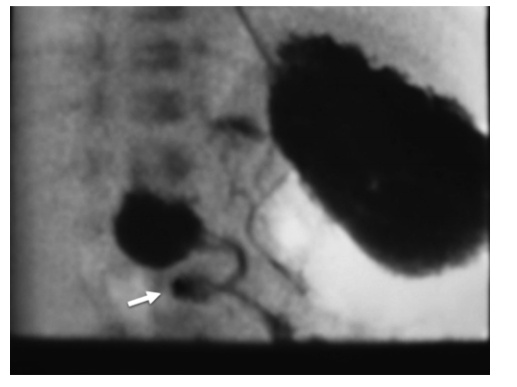

The classic radiographic sign associated with duodenal atresia is the “double bubble” sign on abdominal radiography.

The double bubble is denoted the higher, larger, left-sided stomach bubble together with the lower, smaller, right-sided bubble of the dilated proximal duodenum.

corkscrew appearance (white arrow)

The gold standard for diagnosing intestinal malrotation is an upper gastrointestinal series. Ultrasound imaging is also associated with a 0% false positive rate in the hands of an experienced user.